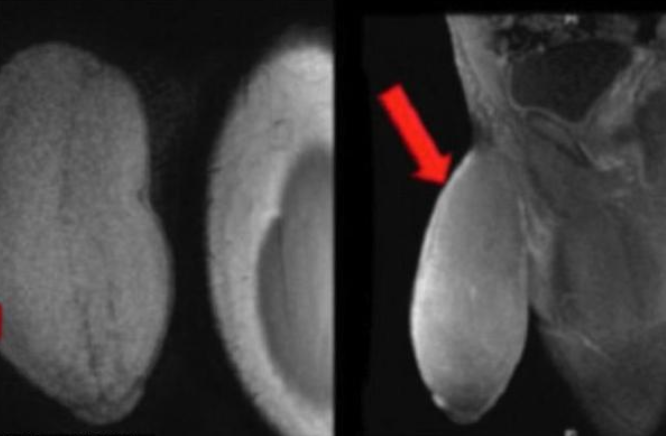

Ο έφηβος είχε πέος μήκους 18 εκατοστά αλλά η περιφέρειά του πέους του ήταν αυτή που έκανε την διαφορά, με διάμετρο 25,5 εκατοστά, έμοιαζε με μπάλα του ράγκμπι, σύμφωνα με τον ουρολόγο και εμπόδιζε τον 17χρονο να αθλείται, αλλά και να έχει σεξουαλικές επαφές.

Η ζωή του 17χρονου είχε γίνει εξαιρετικά δύσκολη, όπως ο ίδιος εξομολογήθηκε στους γιατρούς, αφού εξαιτίας αυτού του μεγέθους δεν μπορούσε να έχει στύση λόγω του περιορισμού της φυσικής ροής του αίματος αλλά και επειδή ό,τι ρούχα και να φορούσε το πέος του ξεχώριζε.

Ο 17χρονος υπεβλήθη σε επιτυχή επέμβαση μείωσης πέους και η περίπτωσή του δημοσιεύθηκε στο ιατρικό περιοδικό Journal of Sexual Medicine, στο οποίο οι επιστήμονες δηλώνουν ότι είναι η πρώτη φορά στον κόσμο που αντιμετώπισαν παρόμοια περίπτωση.